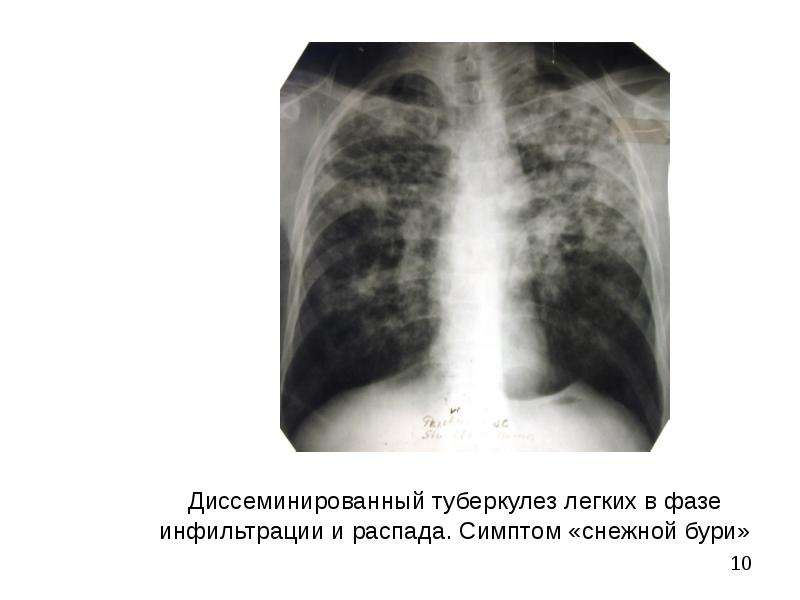

Симптомы туберкулеза: Как распознать и что делать

Раздел: Визуальные уроки